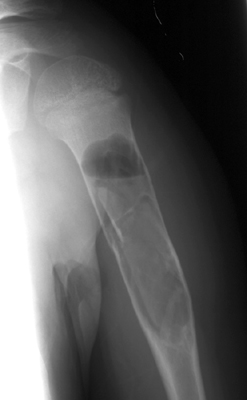

Unicameral bone cyst

Two radiographs of a pathologic fracture in a simple bone cyst of the proximal humerus. Within the cyst is noted a small, thin, linear bony fragment which is displaced from the site of the fracture. An excellent sign of unicameral bone cyst. The fallen fragment secondary to pathologic fracture is pathognomonic for this cyst. A portion of the wall of the cyst has undergone a pathological fracture and subsequently floated down (fallen) via gravity into the dependent portion of the cyst.

- Click on the image for a larger versionA - Click on the image for a larger versionB